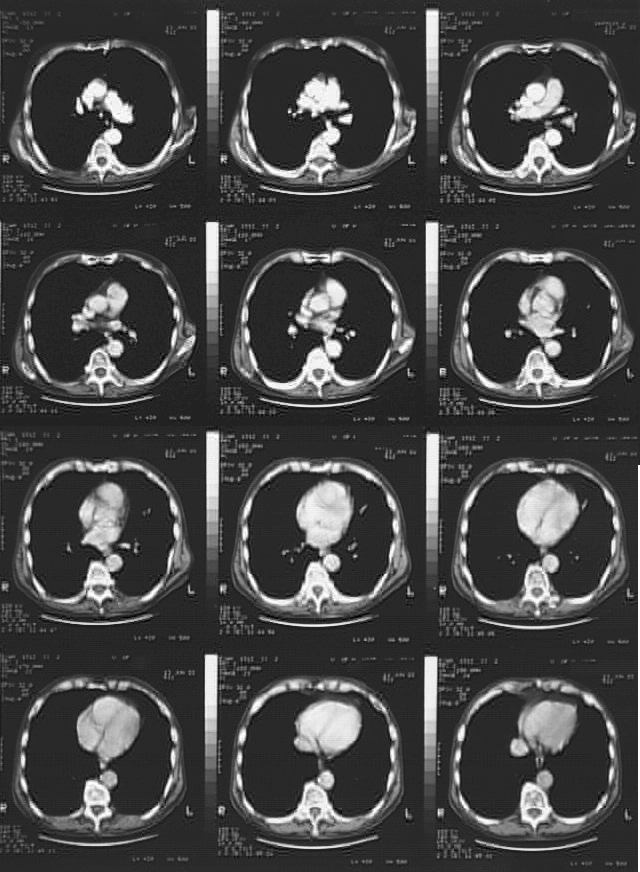

Radiology Images

Thorax- Chest CT June 2